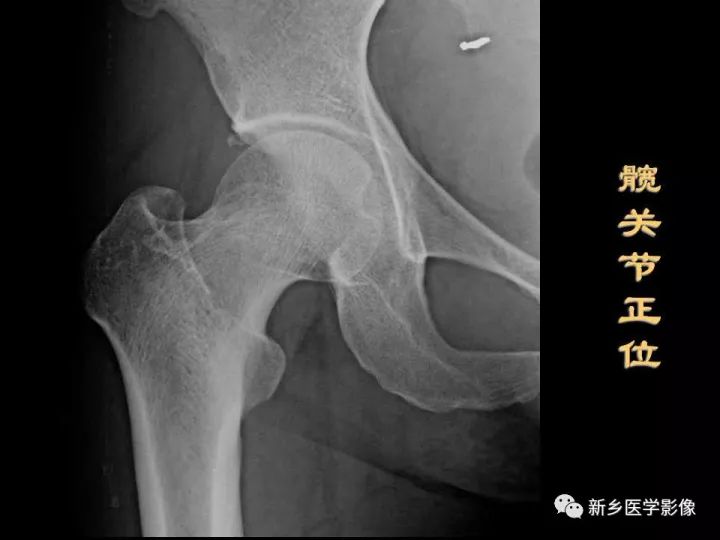

髋骨的X线解剖

常规投照正位(图1)。在X线像上,构成髋骨的三个部分融合于髋臼,可清晰分辨。髂骨翼的内侧1/4影像与骶骨影像重叠,外侧3/4因有髂窝而较透亮。髂嵴阴影较致密,边缘不光滑,外侧可见髂前上棘影,髂后上棘则重叠于骶骨影内。

弓状线及骨盆腔内侧壁形成复合影像,外侧可见弧形的髋臼阴影。髋臼阴影的上段粗而致密,中段较细,它向下绕过髋臼切迹前部的下缘,与耻骨体的内面形成一条“U”形的致密线,称为泪滴线(Koekler泪滴),泪滴线二脚之间的距离,即髋臼窝的厚度。

髋臼内下方的透亮影为闭孔。闭孔影的上界是耻骨上支、外侧界是坐骨体的下份,坐骨结节阴影与其重叠。坐骨棘的阴影呈三角形突向盆腔。

髋关节的X线解剖

常规拍摄正位(见图1)和侧位X线片。正位线片上,因髋臼三骨之间以“Y”形软骨相连,融合之前,表现为横行带状透亮影,其宽窄随着年龄变化而改变。年龄越小此透亮带越宽;年龄越大,透亮带变窄,15~17岁左右消失。股骨头大部套在髋臼内,表面光滑,为致密的细弧线。头的中心偏后下部有一小凹陷,是股骨头凹,有时可投影到股骨头弧线内侧,显示为小环形透亮圈。侧位片上,中央的凹窝是髋臼,呈半圆形的致密线。

图1 骨盆正位片